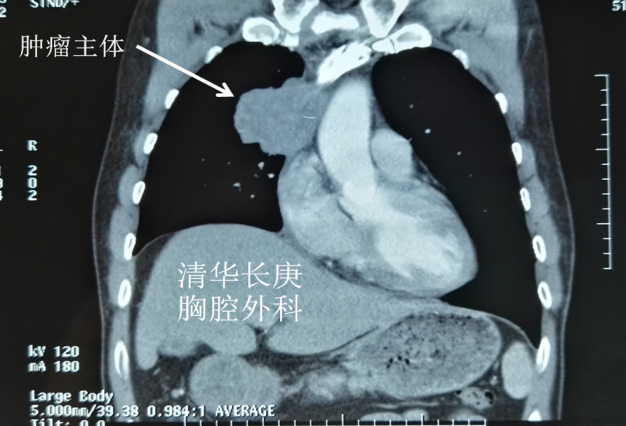

病例1——右肺上叶癌侵及肺门、左右无名及上腔静脉、右心房、心包及纵隔胸膜,行心包内右全肺、部分右心房、上腔静脉切除,人工血管原位置换术。

右肺上叶癌侵及心脏大血管分期为T4,常被认为无法切除,患者失去手术机会。既往不断有尝试切除并获得较好预后的报道,但手术难度大、围术期死亡率高仍是主要问题。此患者就诊前曾于外院行气管镜活检,病理提示肺腺癌。同时未见远处转移,具备手术指征。久经转诊的多家医院均认为无法手术。患者临床表现以上腔静脉阻塞综合征为主(头面部肿胀、静脉曲张、呼吸困难),成功切除肿瘤才能得到缓解。

手术采用胸骨正中切口,进胸后细致分离肿瘤与胸骨间粘连,充分探查后可见肿瘤侵及肺门、左右无名及上腔静脉、右心房、心包及纵隔胸膜。陈东红主任认为为达到R0切除,需进行右全肺、上腔静脉切除,人工血管重建。材料采用Gore-Tex带环人工血管,先以人工血管建立左无名静脉-右心耳血管桥,进一步心包内切除右全肺及受肿瘤侵犯的部分右心房,手工牢固缝合右心房,整块切除肿瘤后搭右无名静脉-右心耳血管桥。进一步彻底清扫纵隔淋巴结。完成手术后可见人工血管充盈,心脏搏动有力,血液动力学指标平稳。切除肿瘤标本直径约8cm,手术时间约7小时。